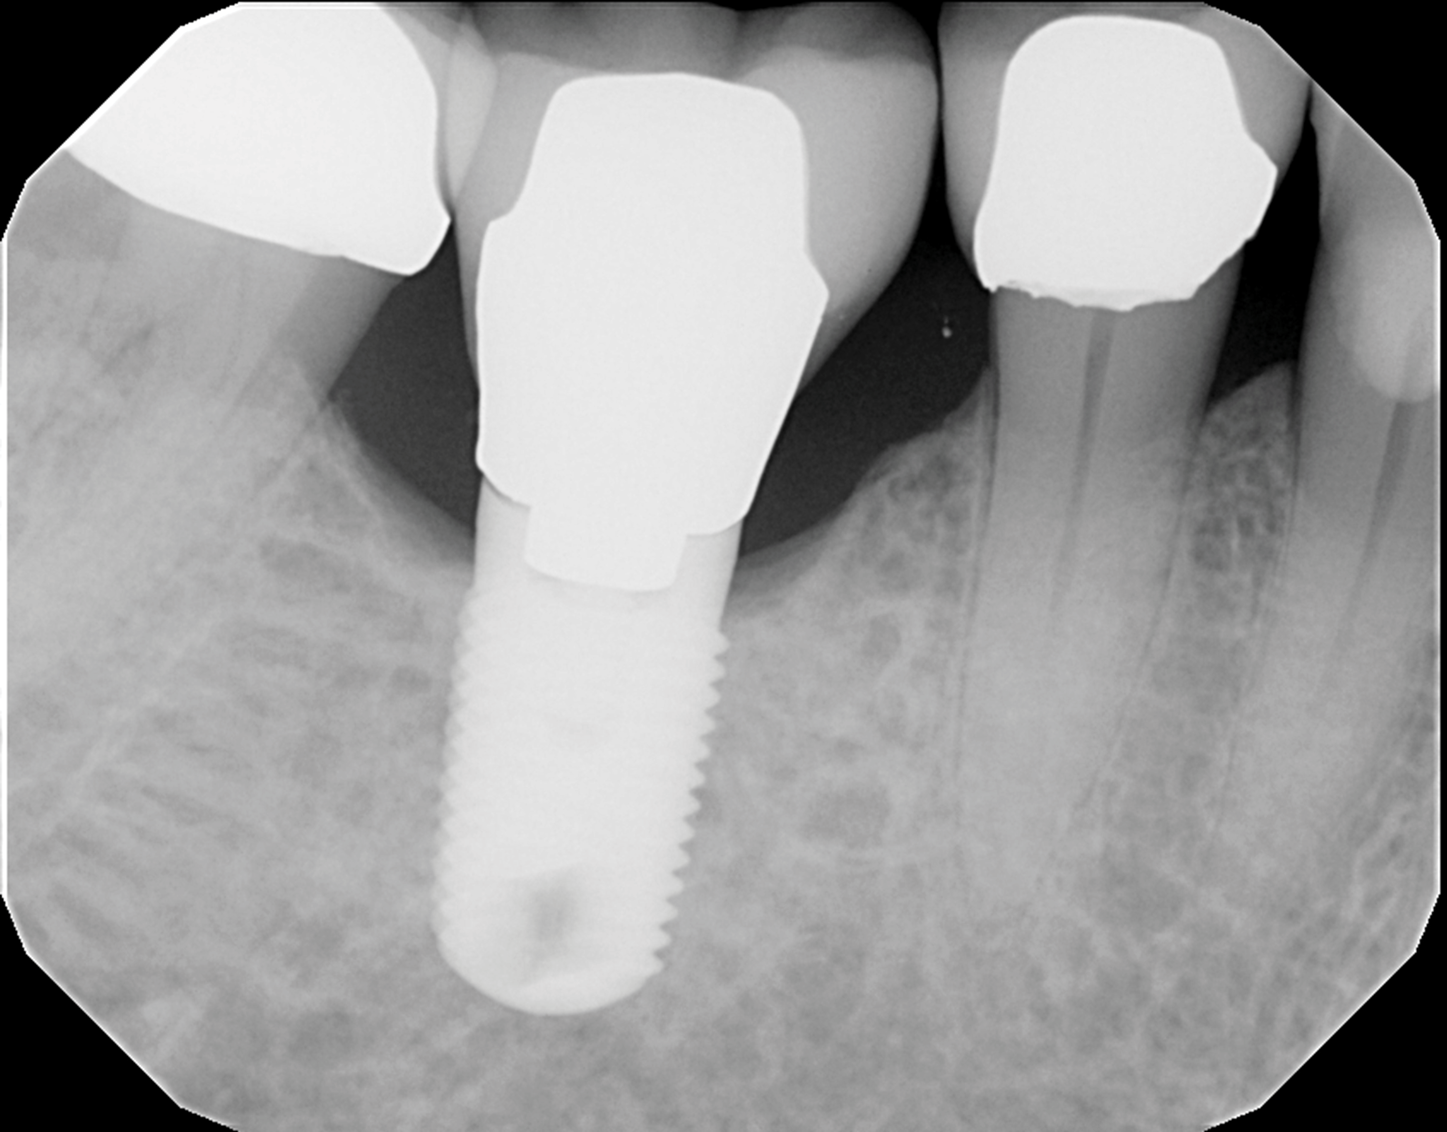

The patient's radiographic assessment, performed immediately following the initial clinical evaluation, included a panoramic radiograph (Figure 4) and bitewing and periapical radiographs of No. 30 (Figure 5). Panoramic findings showed generalized horizontal bone loss confined to the coronal third (15% to 20%), with circumferential bone loss, also referred to as "cupping," around both of the patient's implants, Nos. 30 and 13.

Among the criteria for implant "success" defined in the literature is marginal bone remodeling of less than 2 mm in the first year and no more than 0.2 mm each year thereafter.28 The patient's physiologic bone loss, negative clinical symptoms, and the fact that the implant was placed more than 7 years ago supported the view that the mobility was likely due to a mechanical failure in the abutment rather than peri-implantitis. Given this background, the patient was referred to a prosthodontist to replace both the broken implant component and cement-retained implant crown. No peri-implant surgical treatment was indicated.

Fig 5. Periapical radiograph of implant No. 30, which helped in the evaluation of the extent of the cupping defect seen around the implant site.

Figure 5